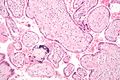

تتكون المشيمة من أنسجة من الأم ومن الجنين. وبعد الأسبوع الأول من الحمل، يلصق الجنين نفسه بجدار الرحم (العضو الذي ينمو فيه الجنين). وتتكون المشيمة كأعمدة من الخلايا من المشيماء (غطاء يشبه الكيس يحوي الجنين) تخترق وتنفذ خلال البطانة الرحمية. وفي داخل الأعمدة، توجد أوعية دموية تتفرع إلى نتوءات صغيرة تشبه الأصابع تُسمى الزغابات. والزغابات التي تحتوي على دم الجنين محاطة بدم الأم. ولا يختلط دم الجنين بدم الأم.

تنشأ من خلايا الطبقة المغذية استطالات شعاعية صغيرة تشكل الزغابات villus تظهر بينها أجواف صغيرة متفرقة. ولهذه الزغابات قدرة حالة للبروتين فتفتح الأوعية الوالدية وينصب محتواها في الأجواف بين الزغابات ويبدأ بذلك الدوران الوالدي - المشيمي.

تختلط الأجواف بين الزغابات بعضها ببعض مشكلة في وسط الطبقة المغذية حجيرة متمادية كبحيرة دموية محصورة بين الطبقة الخلوية المماسة لغشاء الرحم من جهة (الصفيحة القاعدية decidua basalis) والطبقة الخلوية المماسة للمضغة (الصفيحة الكوريونية chorial) من جهة أخرى. وتلتصق الصفيحتان القاعدية والكوريونية في محيط المشيمة التصاقاً وثيقاً. وفي هذه الحجيرة الدموية ينصب الدم الآتي من غشاء الرحم من جهة، وتسبح فيها الزغابات الكوريونية الجنينية المنشأ من الجهة المقابلة.

أما الزغابات التي تحمل تفرعات الشرايين والأوردة السرية فتبرز في الحجرة بين الزغابات بحالة انتعاظ حقيقي لفرق الضغط في داخل الزغابة (48 ملم من الزئبق) وفي الحجرة بين الزغابات (10 ملم). فالدوران الوالدي إذن يبلغ الحجرة بين الزغابات، في حين يفصل الدوران الجنيني عن الحجرة جدران الزغابات المحيطة بأوعيتها، ومن خلال هذه الجدران تحدث المبادلات المختلفة بين الدمين. وعلى الرغم من هذا فقد ثبت وجود بعض عناصر دم الجنين في دم الأم بكميات قليلة جداً، والعكس صحيح.